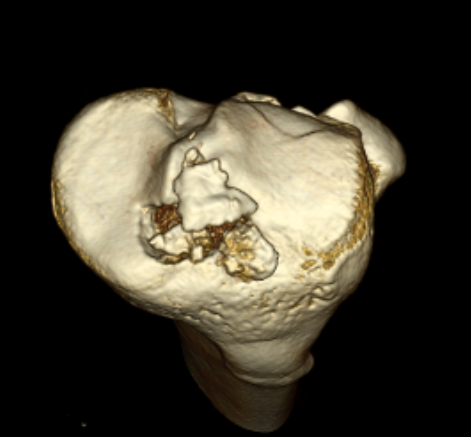

CT

Can help classify and thus guide treatment

Type II Type III

Type IV